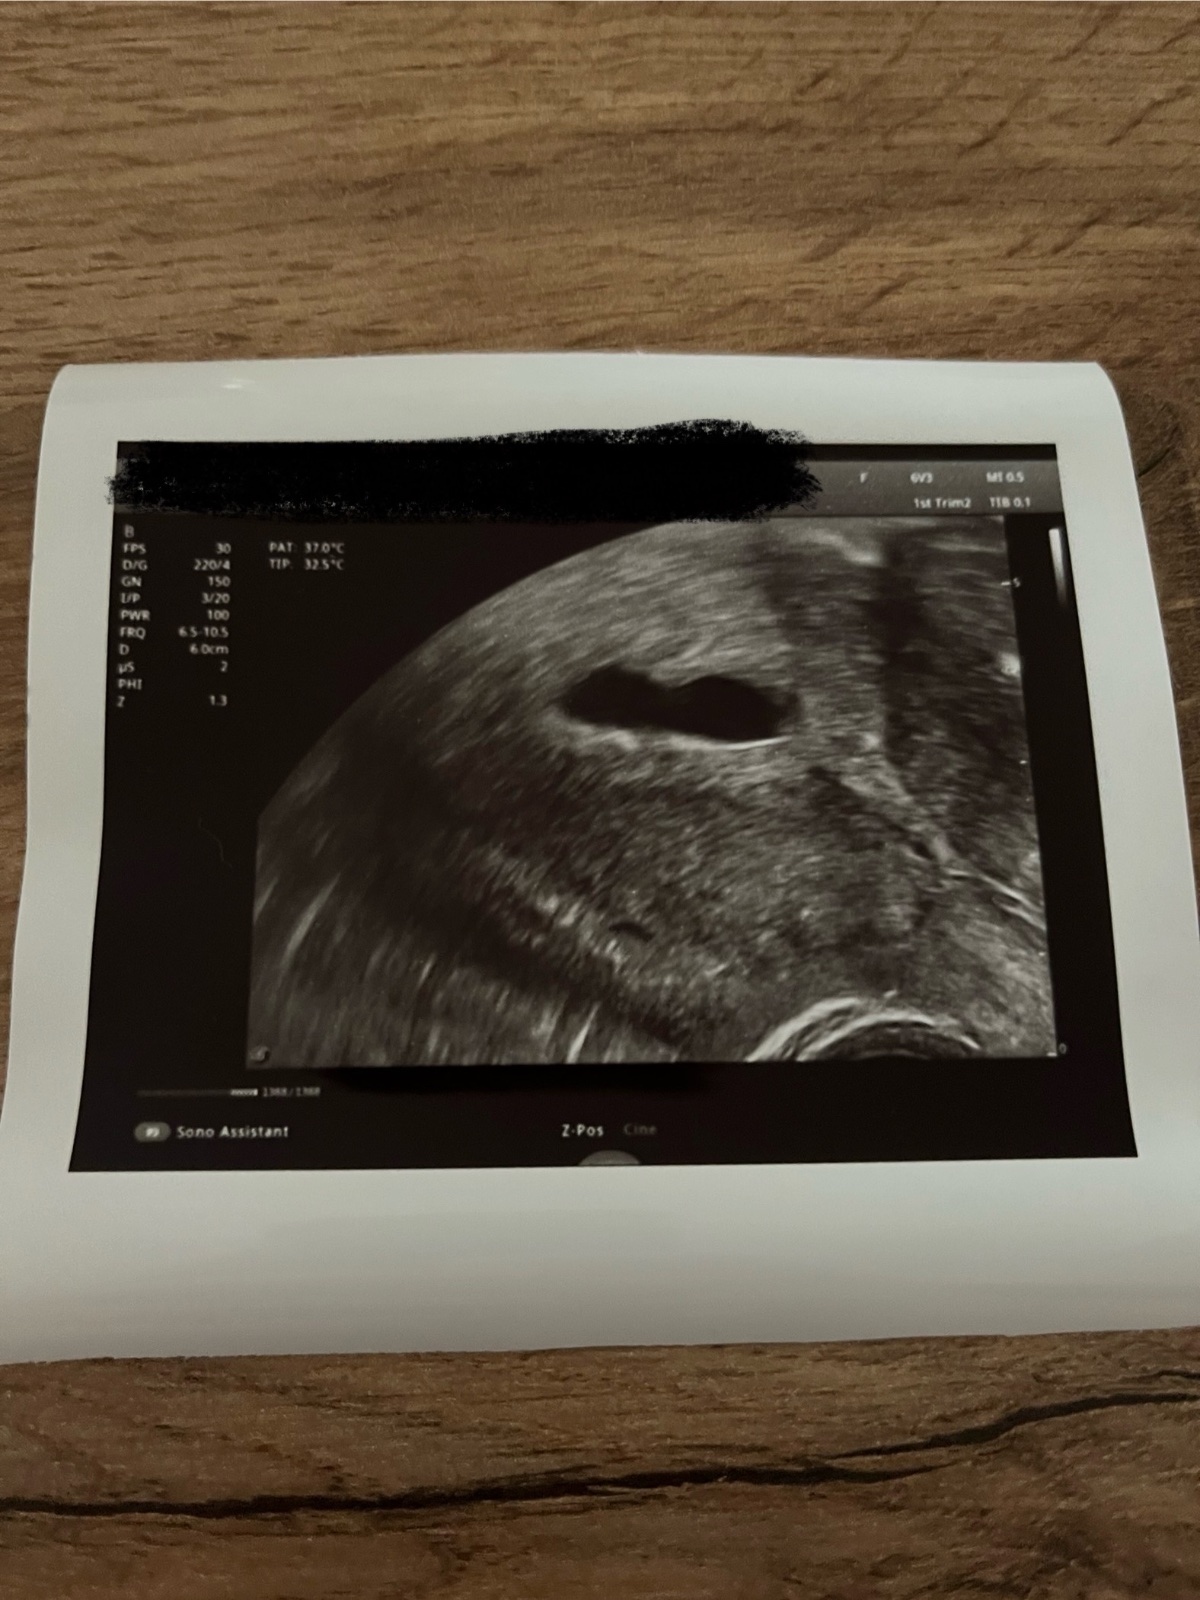

byla jsem u lékaře a ten potvrdil těhotenství, prý 4. - 5. tt. Nemůžeme soudit podle MS, mám nepravidelný cyklus (30 - 47 dní). Pan doktor říkal, že vypadá vše dobře a také, že vidí dokonce srdíčko, ale není ta "dutinka” nějaká zvláštní?

děkuji za Váš dotaz. Tvar generačního váčku nemusí být úplně okrouhlý, bývá poměrně variabilní. Také závisí na řezu, jak je ultrazvukový obrázek zachycen. Na obrázku zárodek zachycen není, ale je podstatné, že Váš lékař zárodek viděl i jeho srdeční akci. To je to hlavní. Vyčkejte tedy do další kontroly.